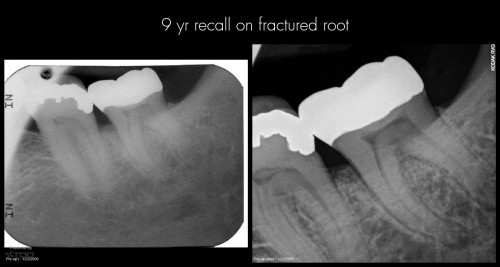

How to avoid fractured roots

By JK / July 31, 2018

In today post recent symptoms on this tooth I retreated in 2010. Short-term followups from […]

By Gary Carr / July 31, 2018